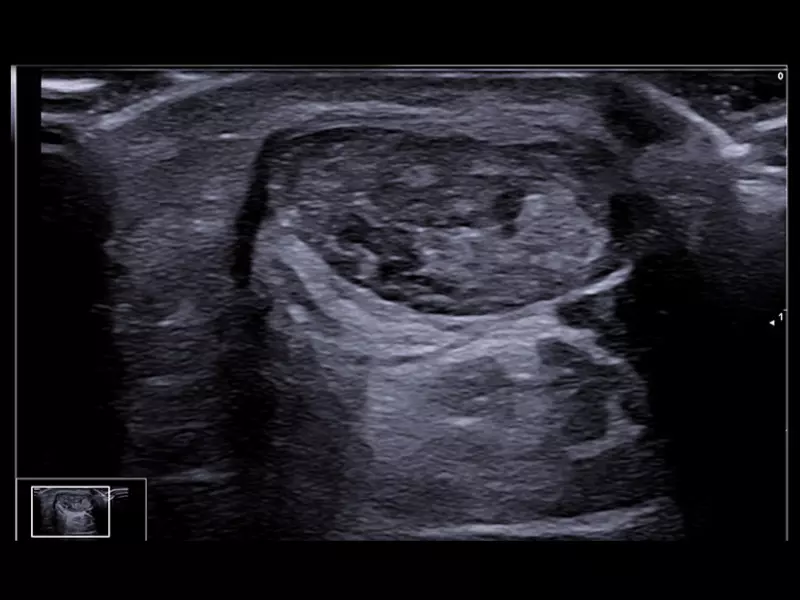

Q7 - WH Spine

Q7 - WH Spine